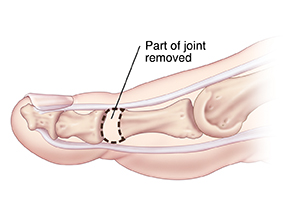

Arthroplasty

A part of the joint is removed, and the toe is straightened. In some cases, the entire joint may be replaced with an implant. When healed, the bones become connected with scar tissue, making your toe flexible.

| Arthroplasty. |